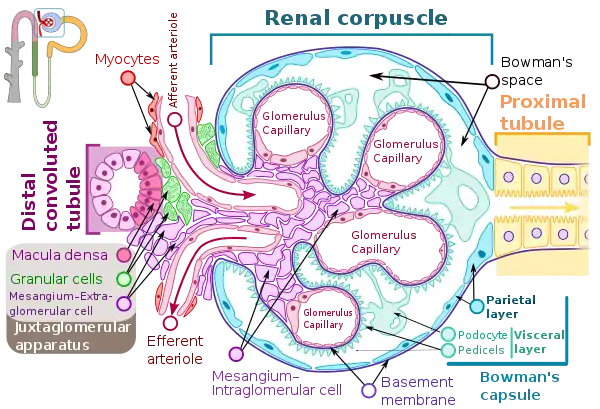

TEM of negatively stained proximal convoluted tubule of Rat kidney tissue at a magnification of ~55,000x and 80KV with Tight junction. Renal corpuscle

Renal corpuscle Diagram outlining movement of ions in nephron.